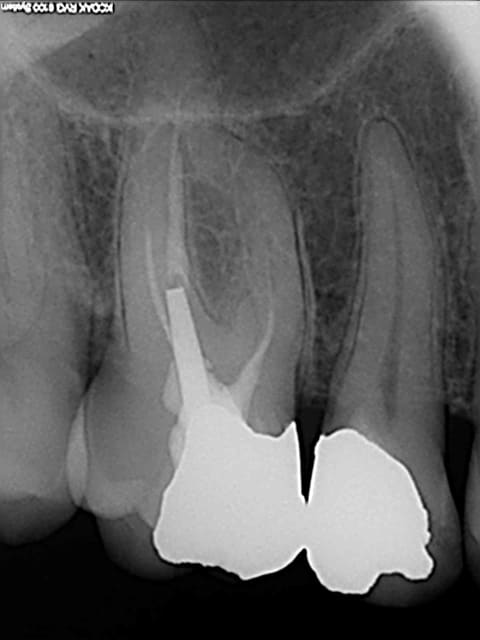

petit jeu:

A vous de trouver quelle endo a été faite au thermafill et laquelle au gutta condensor?

On s'amuse comme on peut... ;-)

Endo1 t7u4v7 - Eugenol

Endo2 dyxj7s - Eugenol

Endo 2 : Thermafil

En général le thermafil est moins radioopaque que la gutta thermocondensée, donc j'aurais plutôt dit la 1, mais c'est vrai que sur la 2 tu as probablement quatre canaux, ce qui augmente la densité et les bouts font un peu "pointu" laissant penser que les tuteurs se sont peut être un peu décalés...

1/Thermafill( on croit apercevoir les tuteurs)

2/gutta condensor ,( je crois voir une spirale dans l' un des canaux mesiaux! )

1:thermafill

Et bien je vois que tout le monde n'est pas d'accord...

endo1 a été fait au gutta condensor

endo 2 au thermafil.

Seul Marc a eu du nez la dessus. ;-)

Comme quoi, radiologiquement, difficile de faire le distinguo entre ces deux méthodes.

Reste à voir au niveau microscopique où l'on peut supposer que la gutta du thermafil a plus de propension à s'insinuer dans les gros canaux latéraux. Pour les petits canaux latéraux, on peut penser que leur obturation est plutôt réalisée par le ciment de scellement canalaire.

C'est la rectitude de l'obturation dans le dernier millimètre apical, surtout sur le canal distal qui m'a mis sur la voie.

Image 1 thermo condensation.

La compression de la technique a provoqué la fusée au niveau de la racine distale de 36.

image 2 thermafil

Je crois apercevoir la pointe du tuteur thermafil sur racine distale de 46.